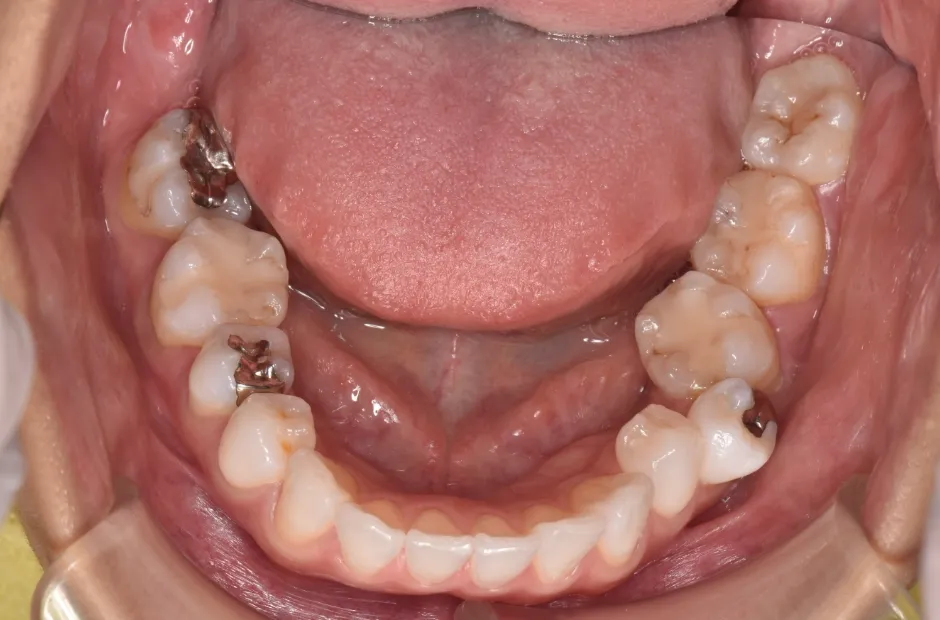

治療前

叢生

| 診断名・主訴 | 叢生 |

|---|---|

| 年齢・性別 | 43歳・女性 |

| 治療期間・回数 | 2年7か月 27回 |

| 治療に用いた主な装置 | 舌側矯正 |

| 抜歯部位 | 両顎4,4 |

| 治療費 | 100万円(税抜) |

| リスク・副作用 | 装置による違和感・疼痛・歯肉退縮・歯根吸収・虫歯のリスクなど |